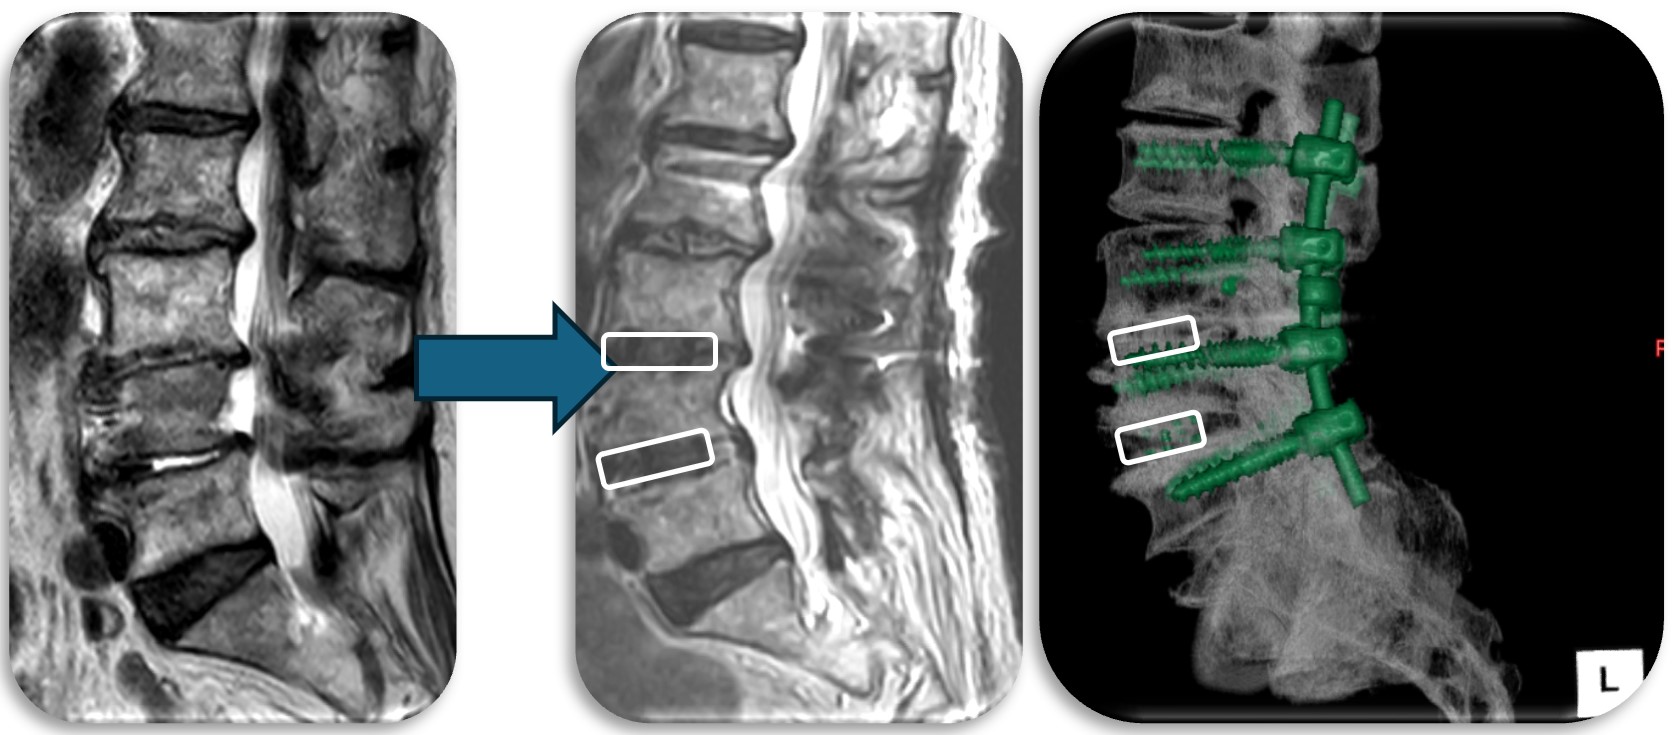

(代表例②)

腰部の脊柱管狭窄症に対して、腰の後ろから手術する椎弓切除術を行なった症例です。脊柱管と呼ばれる脊髄が通るトンネルの屋根部分にあたる椎弓を切除(点線部分)することによって狭かった脊柱管を広げます。

(代表例③)

腰部の脊柱管狭窄症に対して、腰の側方から徐圧し、後方から固定術(OLIF)した症例です。椎間板が摩耗していたり、不安定性がある症例、後方からの手術歴があり再手術症例に適した手術方法です。狭小化した椎間板にスペーサーを挿入(白線)する事により、脊柱管の高さを正常な状態に戻し3次元的に狭窄を改善させます。